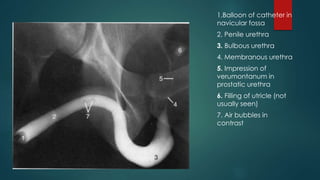

1.Balloon of catheter in

navicular fossa

2. Penile urethra

3. Bulbous urethra

4. Membranous urethra

5. Impression of

verumontanum in

prostatic urethra

6. Filling of utricle (not

usually seen)

7. Air bubbles in

contrast